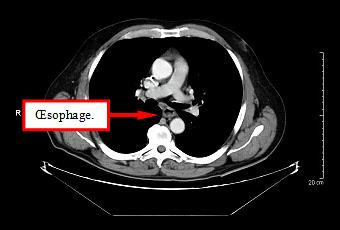

Le cancer de l'oesophage est un cancer peu fréquent en France, 5 000 cas par an.

Source iconographique et légendaire: http://www.radiotherapie-hegp.fr/artec/cancer-de-l-oesophage